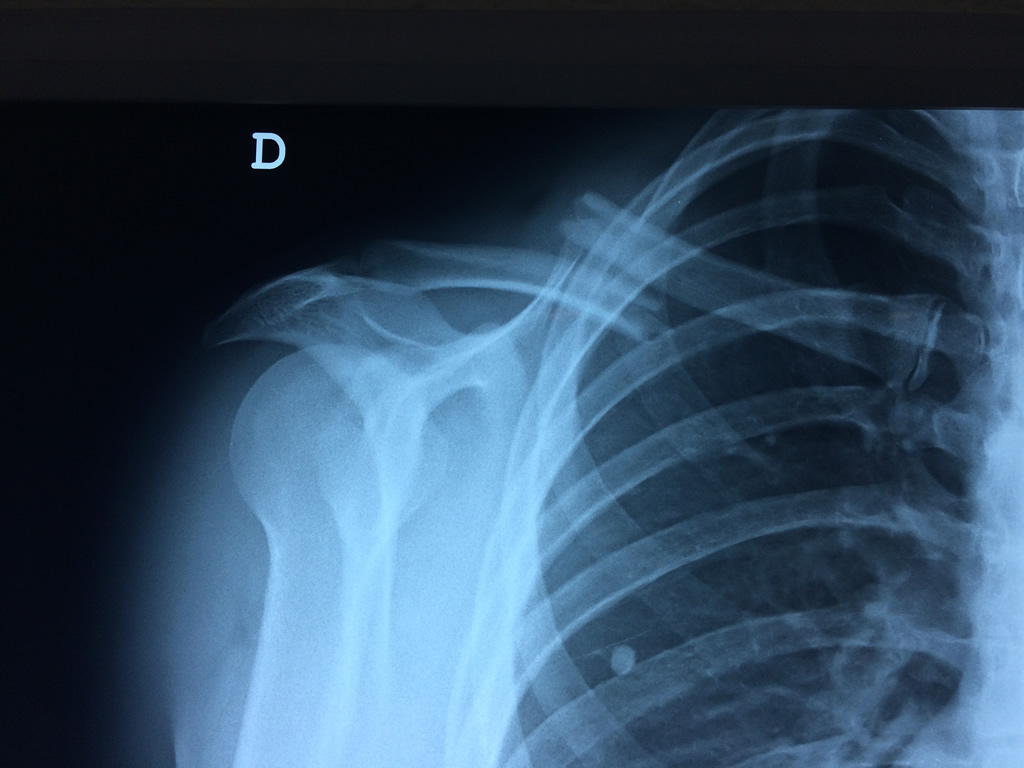

Fémur - Clavícula

La clavícula es un hueso largo, con forma de "S" itálica, situado en la parte anterosuperior del tórax. Junto con la escápula forman la cintura escapular. Se puede palpar por toda su longitud y se extiende del esternón al acromion de la escápula, siguiendo una dirección oblicua lateral y posterior.

Se considera el único medio de unión entre el miembro superior y el tórax. A pesar de su aspecto, similar al de un hueso largo, posee una estructura semejante a la de un hueso plano, ya que carece de epífisis y de diáfisis, lo que la harían entrar dentro de la clasificación de hueso largo. Carece de un canal medular propiamente dicho.